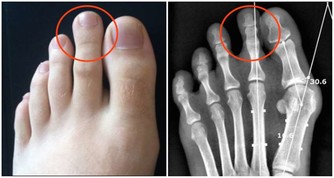

久之這些重金屬就會在腎小管內聚集,嚴重時甚至會引起腎小管的壞死。

但這個藥有個很大的毒副作用,就是損傷腎臟,像氨基糖甙類抗生素一樣,引起腎小管壞死。

但最近卻一連發現有3位患者,在進行到第4個療程的時候,出現了不同程度的腎功能受損。

當然,我們首先想到的是順鉑對腎臟的損傷,但這幾個病人的腎臟代償能力怎麼就這麼差呢?

帶著這個問題,我在隨訪中對這幾個病人的飲食習慣問了一下,發現她們的確都和我一樣,喜歡吃蘑菇。